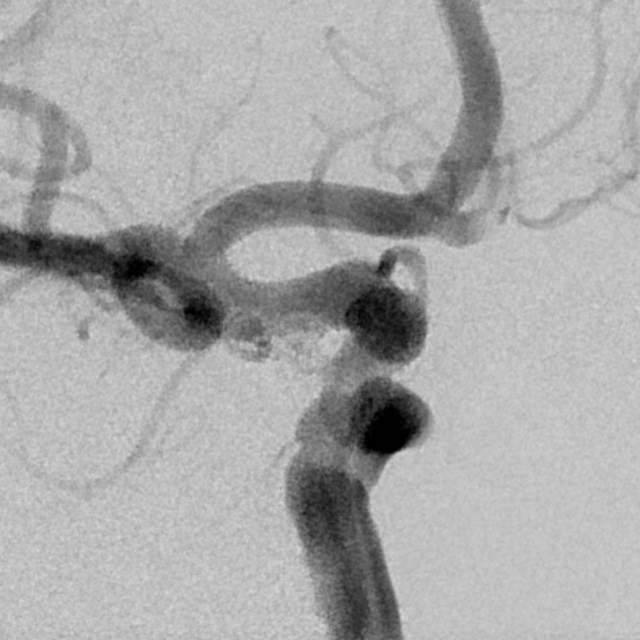

病情变化:中年男性患者,由于头晕查体发现后交通动脉瘤,第一次造影可见形态尚规则,患者及家属经过反反复复的思想斗争,决定采用外科干预。3天后,术中发现动脉瘤的形态已经出现改变,瘤囊的远端出现子瘤。

患者选择:一般而言,这种进展性形态变化伴有子瘤的病变容易出现破裂出血,患者的本次决定真是不失时机的明智之选。

术中评估:动脉瘤位于后交通段的位置,靠近颈内动脉分叉部,颈内动脉交通段的长度相对短小,而且呈现喇叭口的形态,支架不容易锚定,容易出现跳跃“”嗑瓜子”现象。如果支架超过分叉部,覆盖大脑前动脉的起始部,可能会造成后续的大脑前动脉的血管变细。